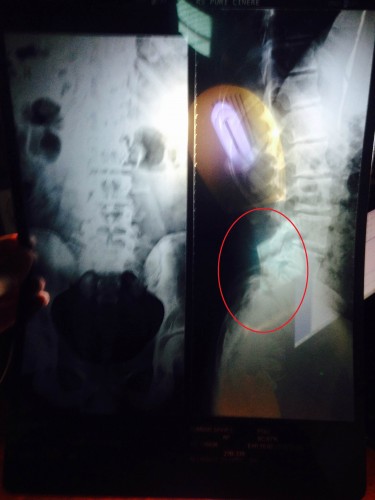

so i tried to go to the doctor and they finally took the pictue with an x-ray

and he said that i have a calcification of bone and a shift of bones.

PS: here are the x-ray pictues